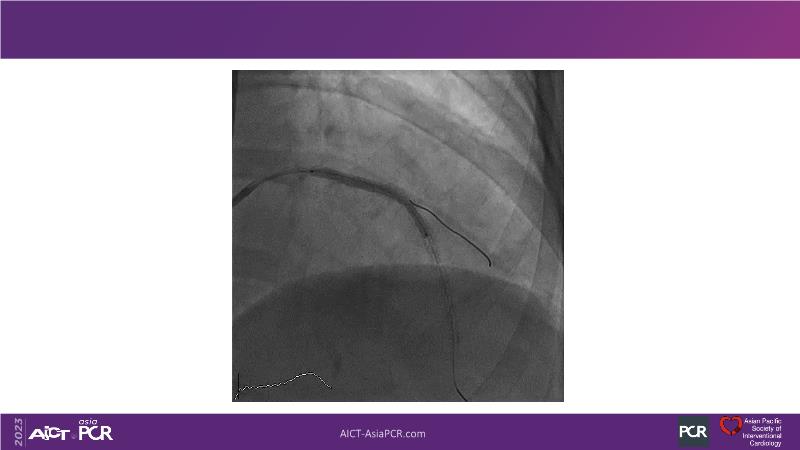

This session is recommended for you if you are seeking insights into the advantages of using IVUS imaging over visual assessment for better outcomes in left main bifurcation procedures. Discuss with experts the benefits of using RotaCUT in lesion preparation for left main bifurcation and explore the impact of high radial strength stents on the procedure's success.

• To understand why the use of IVUS imaging is different from seeing with experienced eyes to achieve improved left main bifurcation outcome

• To see advantages of RotaCUT as part of lesion preparation in left main bifurcation